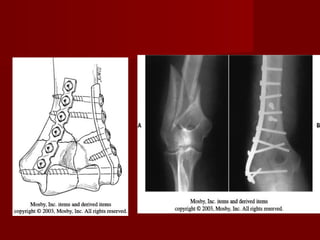

INTERCONDILEAS.

Clasificación de Mehne y

Matta es la que mejor

describe los hallazgos

transquirúrgicos.

Si los fragmentos estan

alineados se trata con

ferula y movilizacion

gradual hasta consolidar

   Cuando              los

fragmentos        estan

desplazados          es

preferible la reduccion

abierta.

   La cirugía se realiza

con mayor facilidad

en las primeras 24 a

48 horas.

    Vía  de abordaje de

Campbell, sus ventajas

son:

1.   Buena exposición de

todas las superficies

articulares.

2.   Lo cual permite libertad

de seleccionar el tipo de

fijación interna.

3. Una vez que el nervio

cubital     a      sido

identificado y retraido

medialmente, no hay

grandes     vasos     o

nervios en el sitio de

la insición